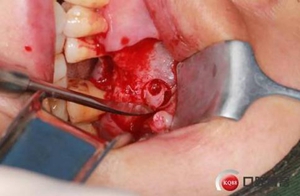

改良式外提升工具盒-外提 科貿(mào)嘉友收錄

六個(gè)月之后